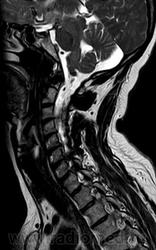

ГМ. СМ. Нейросаркоидоз. Саркоидоз на спинальном уровне. +

Саркоидоз на спинальном уровне.

Нейросаркоидоз